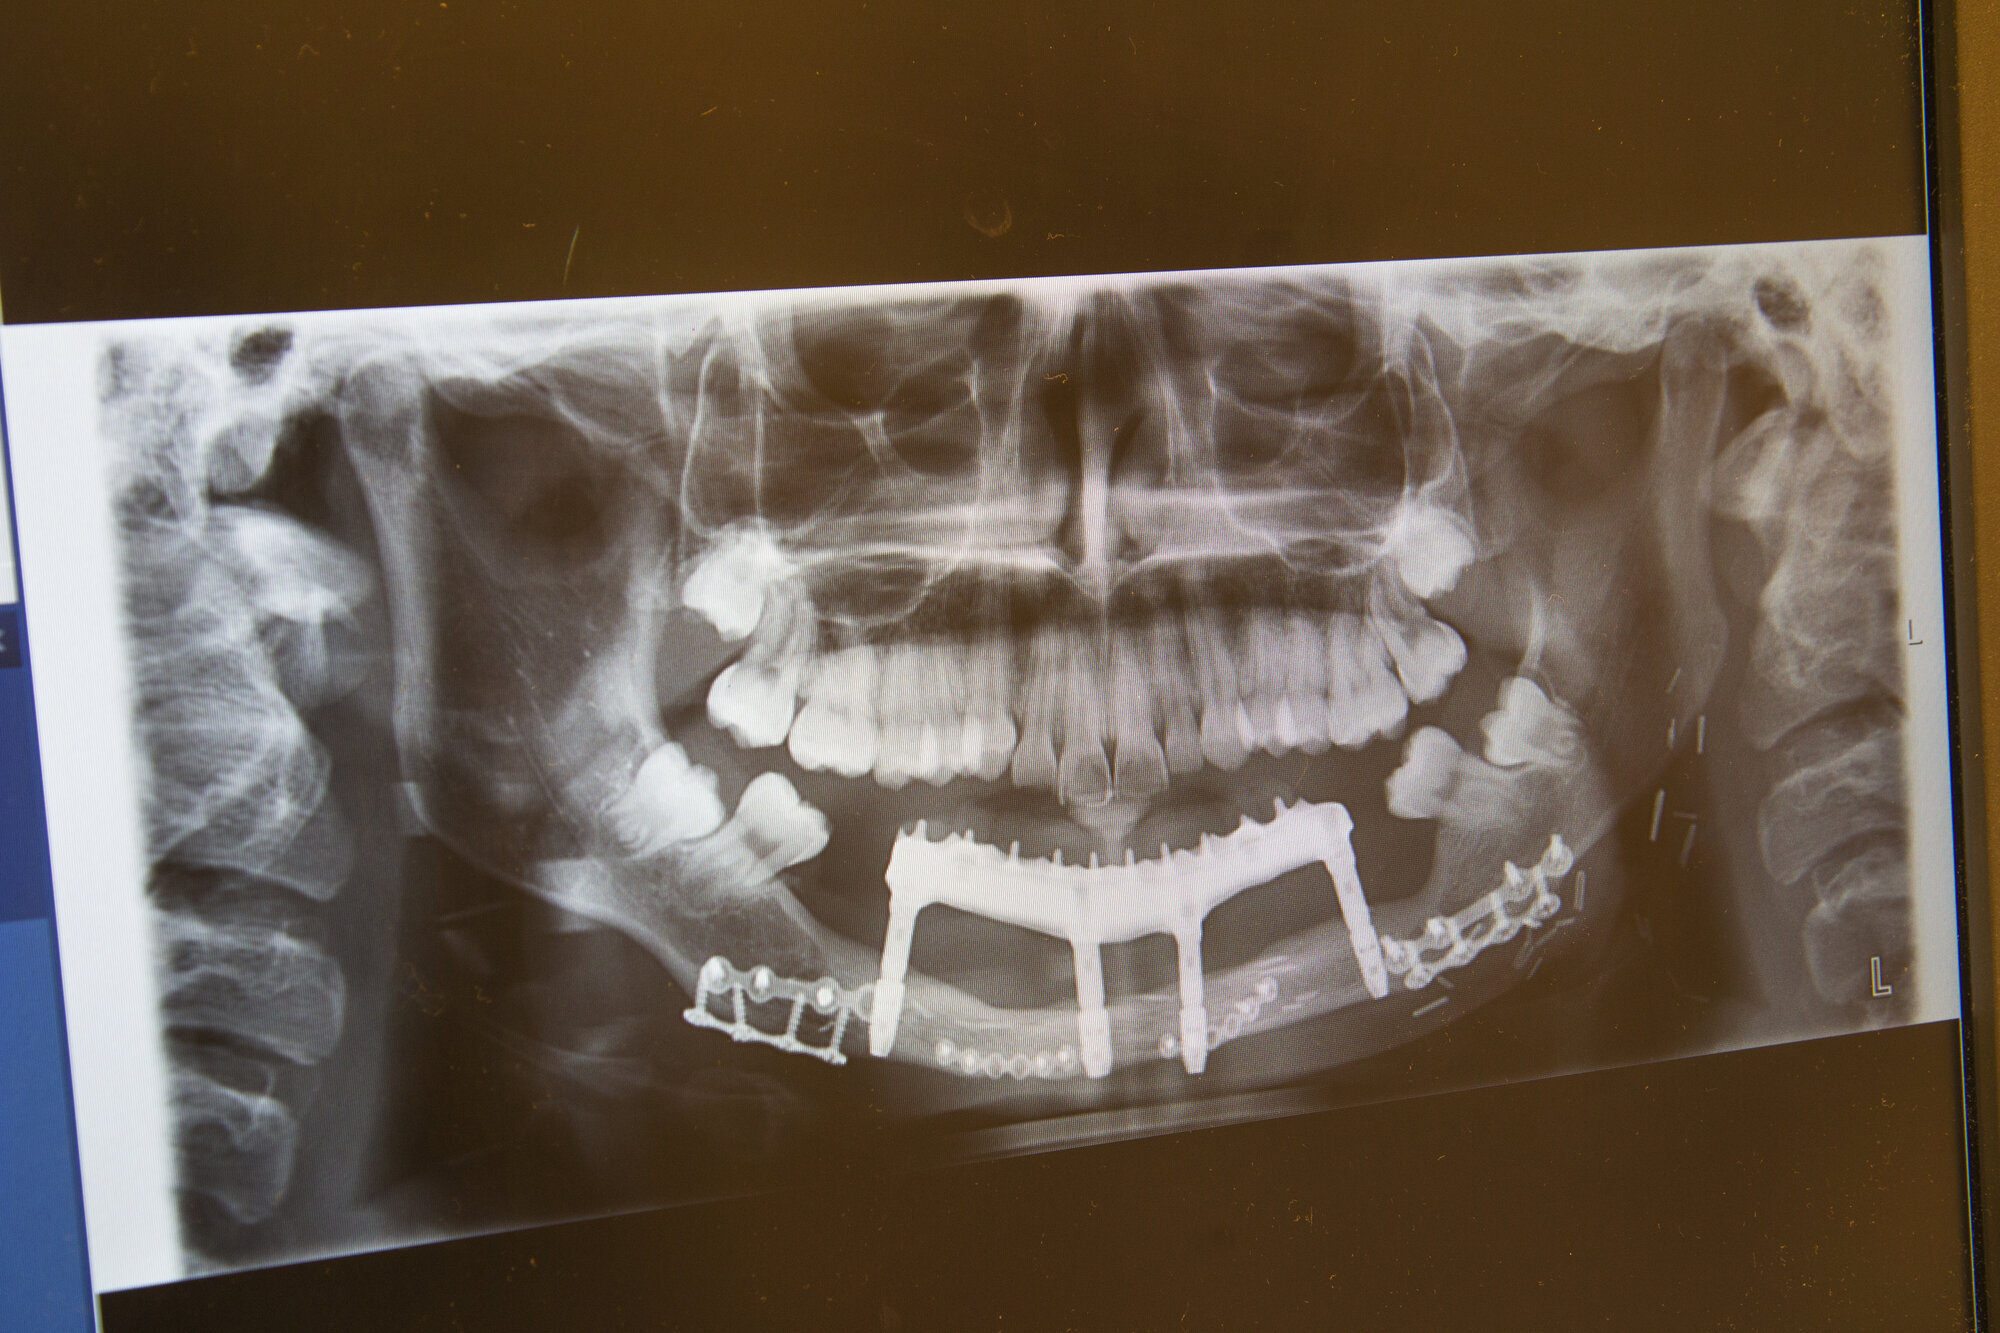

I sjeldne tilfeller rammes barn av beinkreft. På pc-en viser Berstad et røntgenbilde av en tolv år gammel pasient som fikk osteosarkom i underkjeven.

– Tolvåringen, som etter hvert skulle begynne på ungdomsskolen, kunne ikke gå rundt tannløs. Da er det fint å være del av et høyspesialisert sykehus med mange dedikerte spesialister. Alle sto på for å hjelpe. Tumoren og hele kjeven med tenner ble fjernet. Kjeven ble erstattet av en del av leggbeinet (fibula).

I en tolvtimersoperasjon ble både kreften fjernet og ny kjeve rekonstruert. Et svært team var involvert.

Berstad var med på å forme den ny kjeven av leggbeinet. I en senere operasjon satte hun inn fire implantater som ble skrudd ned i kjeven. Hver skrue er en slags kunstig tannrot. Når dette har grodd, skrus tennene fast i implantatene.

(Saken fortsetter under bildet.)